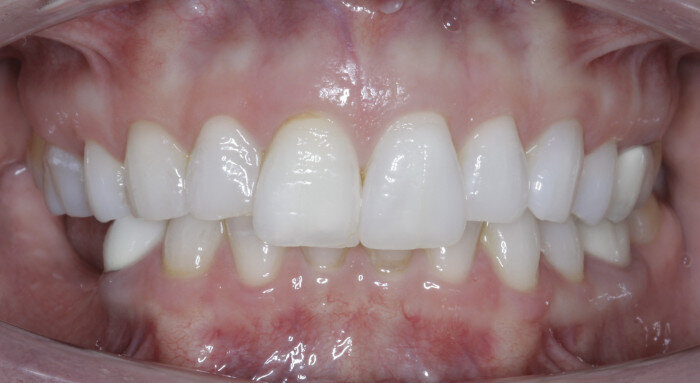

The anterior gummy smile The anterior gummy smile is one in which the patient shows excess gingival display from maxillary canine to maxillary canine (Figs. 4 & 5, beginning of treatment). This takes into account the ideal crown shape and size, where the patient has true anterior maxillary excess and is not just in need of a gingivectomy or crown lengthening procedure. To best determine if gummy smile treatment is needed in the anterior, the authentic smile photograph is used, alongside measurement of the incisor display at rest. If the resting incisor display is greater than threequarters in the adult patient without altered passive eruption, gummy smile treatment is needed. These cases are treated using two TADs placed between tooth #13 and #12 or between #22 and #23 using a 1.6 × 6.0 mm TAD. If slight posterior impaction is desired, bite turbos with Triad Gel (Dentsply Sirona) are placed on teeth #37 and #47 and squeezing exercises used to impact posterior molars engaging the posterior fibres of the temporal muscles (60 squeezes six times per day).

Fig. 4

Fig. 5